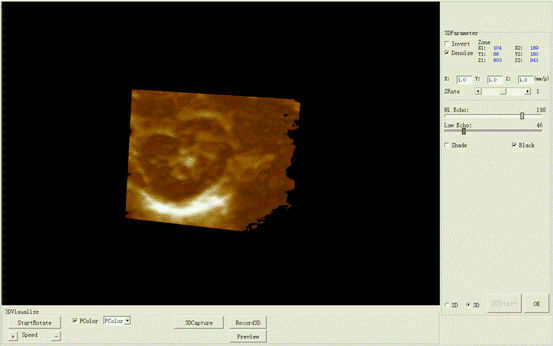

The new Portable Laptop Digital Ultrasound Scanner features a 3.5MHz micro convex probe for versatile imaging capabilities. This compact machine is designed for high-quality diagnostics in various medical settings, providing detailed ultrasound images. Its lightweight design and user-friendly interface make it ideal for healthcare professionals who require mobility and ease of use. The scanner is suitable for a range of applications, ensuring accurate assessments and improved patient care. Overall, it's a reliable solution for modern medical imaging needs.